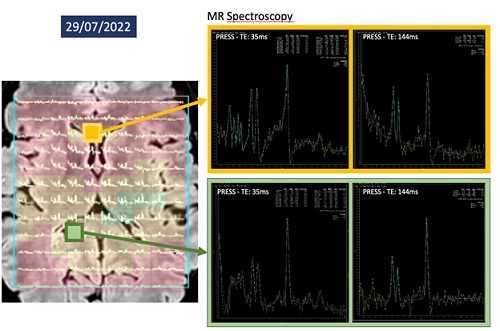

At discharge, the patient displayed balance and subjective visual disturbances (Figure 1). Follow-up MRI showed a reduction in lesion size, although MR spectroscopy showed a decrease in metabolites levels in the splenium compared to the genu of CC (Figure 2).

Figure 2: MRI showed a reduction in lesion size, although MR spectroscopy showed a decrease in metabolites levels in the splenium.